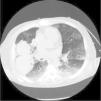

In light of suspected vasculitis, treatment was initiated with three boli of methylprednisolone 500mg on consecutive days, followed by prednisone at 1mg/kg every 24 hours. 72 hours later, symptoms of haemoptysis and anaemia appeared; a chest X-ray and chest CT scan were performed, showing findings suggestive of a bilateral alveolar haemorrhage and the presence of intraparenchymal pulmonary haematoma (Figs. 1 and 2). Treatment was initiated with a bolus of 500mg/m2 cyclophosphamide and immunoglobulins at 2g/kg, spread across five doses. Five days later, frank haemoptysis, anaemia and significant respiratory effort occurred, prompting a transfer to ICU, where orotracheal intubation and mechanical ventilation were performed. The patient also required aspiration due to massive bleeding.

Lung involvement in HSP is extremely rare and includes, above all, haemorrhage or interstitial disease. Diffuse alveolar haemorrhage, which may present immediately following the HSP diagnosis, or even several years later, has an unpredictable clinical evolution and is associated with high rates of mortality.7,8

Chest X-rays are usually non-specific and computed tomography is required to confirm the findings. The severity of the situation warrants the use of intensive immunosuppressive therapy9; treatment combined with glucocorticoids and cyclophosphamide, azathioprine, methotrexate or rituximab is common. Plasmapheresis has also been noted as a therapeutic option.